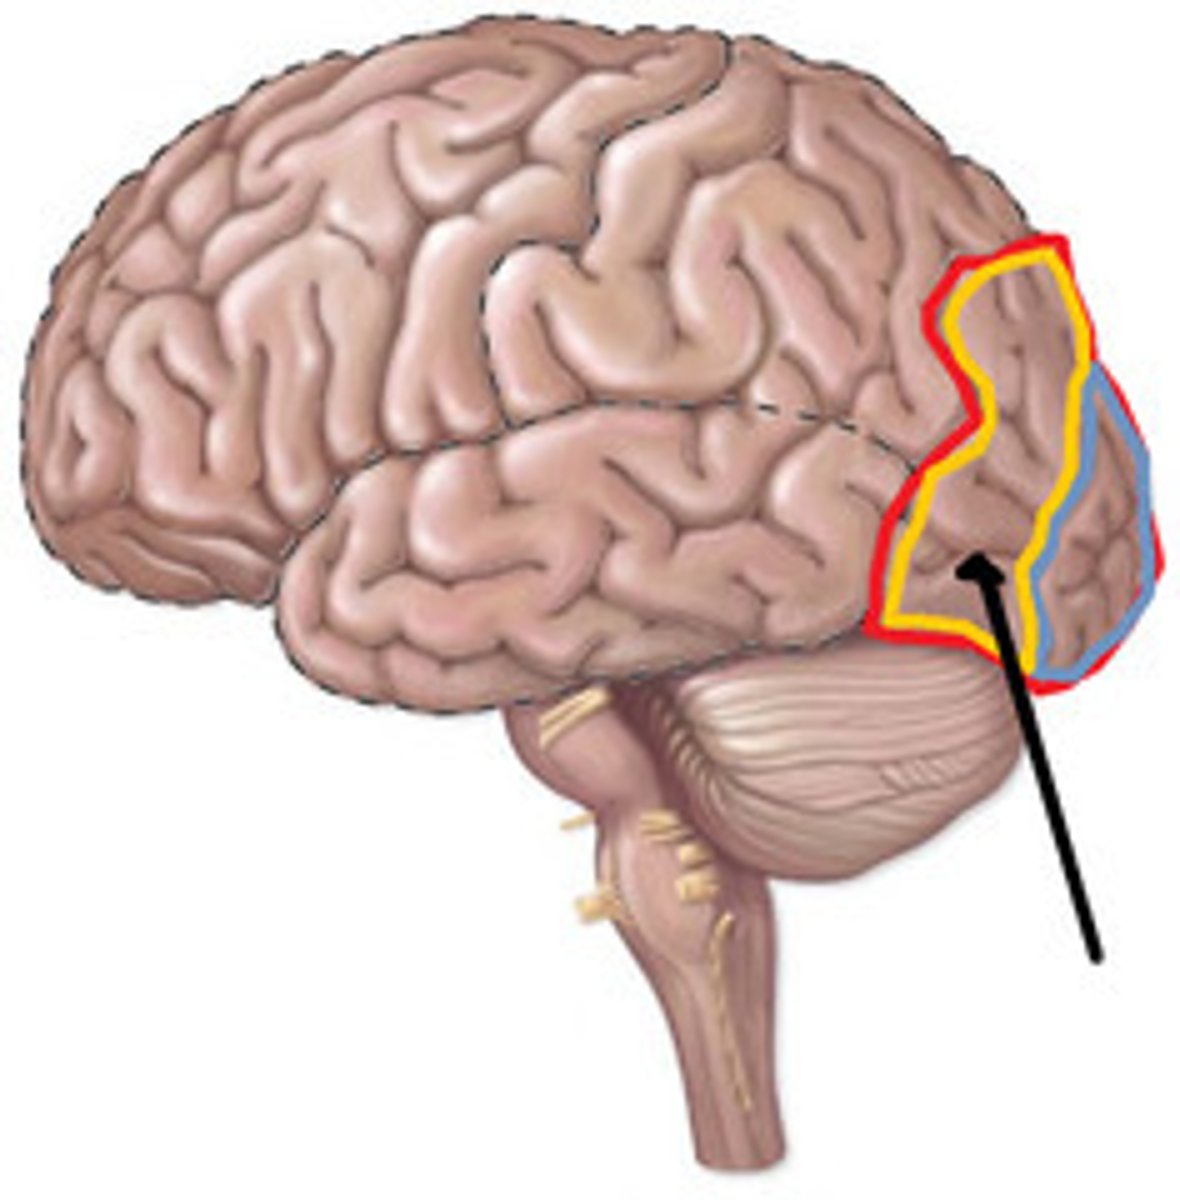

Precentral cerebral gyrus

primary motor cortex of the cerebrum is situated anterior to the central sulcus

postcentral gyrus

the strip of parietal cortex, just behind the central sulcus, that receives somatosensory information from the entire body

lateral cerebral sulcus

separates the frontal lobe from the temporal lobe

parieto-occipital sulcus

separates parietal and occipital lobes